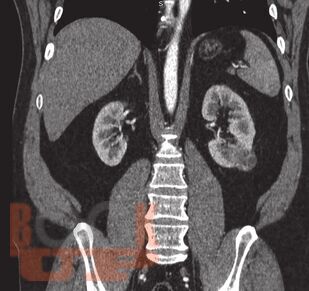

В данном учебном пособии представлены сведения по анатомии и физиологии почек, эпидемиологии, этиологии, патогенезу, клинике, диагностике и современному хирургическому лапароскопическому лечению опухолей почек.